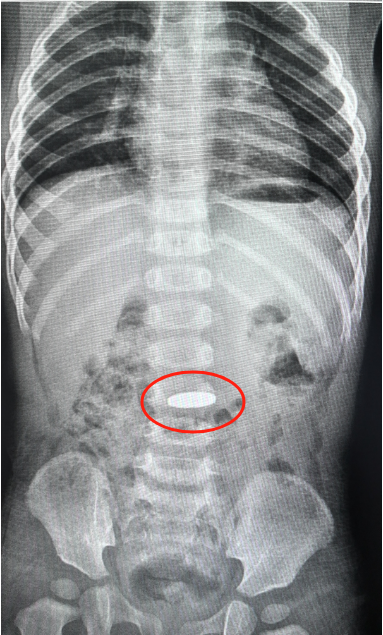

这次腹部立位片检查的结果显示,硬币在孩子的胃里一动没动。接诊的儿科副主任医师王艳丽担心胃酸的腐蚀会对胃粘膜造成刺激,金属异物在胃里呆的时间过长会导致胃粘膜水肿,有些异物甚至会引起胃部糜烂或者溃疡,于是建议让孩子在全麻下进行胃镜下异物取出术。

不到3分钟,王艳丽就将卡在强强胃里的硬币取了出来,整个手术过程迅速而精准。被取出来的一毛钱的硬币,直径约有1.9厘米宽,王艳丽表示,吞进异物有些对人体是有害的,特别像这种金属类的异物或者一些对消化道有潜在危害的异物,如果观察超过72小时未排除,还是建议应及时取出。术后,强强精神状态挺好,没有什么不良反应和副损伤,也能正常进食。